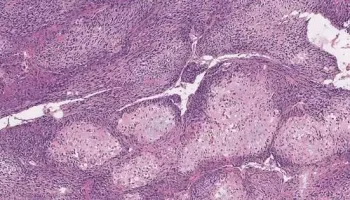

Of the numerous ways of treating disease, the most seasoned, and perhaps generally proven, is a medical procedure. Indeed, even with the coming of chemotherapy,